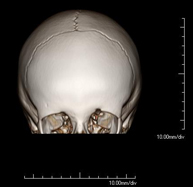

- TC Crani

Prova radiològica que consisteix en obtenir imatges del crani d'alta definició anatòmica (tronc cerebral, cerebel, cervell, calota cranial, etc. ) mitjançant l'ús d'un equip de TC (Tomografia Computeritzada). Indicacions: traumatismes, cefalea, trastorns de la memòria, pèrdua de força sobtada en una extremitat o meitat del cos. - TC Coll